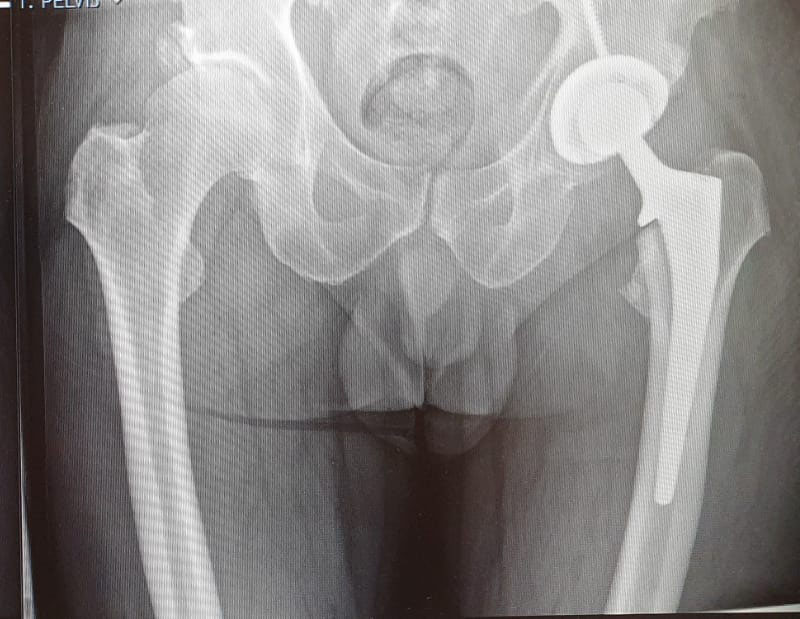

See below for some before and after X-rays of total hip replacement surgeries I have performed to treat Osteoarthritis. Drag the sliders to switch between the before and after images.